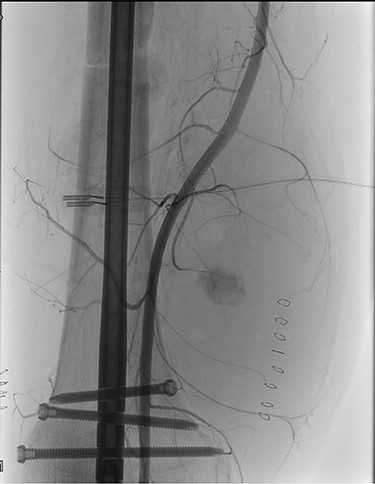

During hospitalization, the patient underwent many orthopedic surgeries for various fractures of the right lower limb, and a centimetric pseudo-aneurysm of the right SFA (Fig. 1), was found at a routine duplex ultrasound of the lower limbs, originating from a small collateral branch of SFA at the distal third of the thigh.

Preoperative angiography showing the pseudo-aneurysm of the right SFA, originating from a small collateral branch of SFA at the distal third of the thigh.

The consultant interventional-radiologist indicated the need for an endovascular repair of the lesion. Through percutaneous puncture of the left common femoral artery, selective catheterization of the right SFA was performed, and embolization of the pseudoaneurysm and the tract of the artery downstream of it, was completed with ONYX 34.